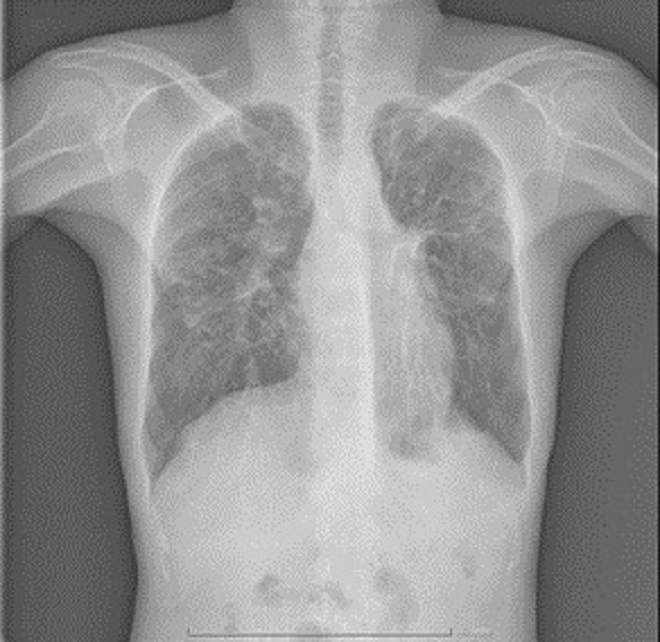

Simptomele pacienţilor cu mucoviscidoză variază în funcţie de vârstă, tabloul clinic al afecţiunii fiind compus din: Retard de creştere la copil, icter prelungit cu caracter obstructiv, ileus meconial (obstrucţia intestinului subţire la nou născut), edeme hipoproteice, transpiraţie sărată (hainuţele nou născutului sunt impregnate cu sare), şi wheezing (respiraţie şuierătoare) la nou născuţi şi sugari; Polipi la copii, durere şi senzaţie de presiune la nivelul sinusurilor faciale, cefalee, dureri abdominale cronice, deshidratare severă cu pierdere excesivă de sare prin transpiraţie, senzaţie de greaţă şi vărsături, scaune moi, deschise la culoare, după consumul de alimente bogate în grăsimi, ascită (acumulare de lichid intraabdominal) hemoroizi, prolaps rectal, întârzierea pubertăţii şi infertilitate (în cazul adolescenţilor de sex masculin); Simptome respiratorii: tuse cronică cu expectoraţie mucopurulentă, foarte rar tuse seacă, dispnee, wheezing, cianoză, infecţii respiratorii frecvente (în special cu Pseudomonas aeruginosa, Stafilococul auriu sau Escherichia Colli, insuficienţă respiratorie cu hipoxie (scăderea cantităţii de oxigen din corp), scăderea toleranţei la efort.

Substituirea enzimatică a deficitului pancreatic pentru creşterea absorbţiei grăsimilor alimentare la nivel digestiv; Complicaţii la nivelul aparatului respirator: bronşiectazii colonizate cu Pseudomonas Aeruginosa, Staphylococcus Aureus sau Escherichia Coli, hemoptizie (tuse cu sânge), pneumotorax, insuficienţă respiratorie, polipoză nazală şi exacerbări (agravarea bolii)